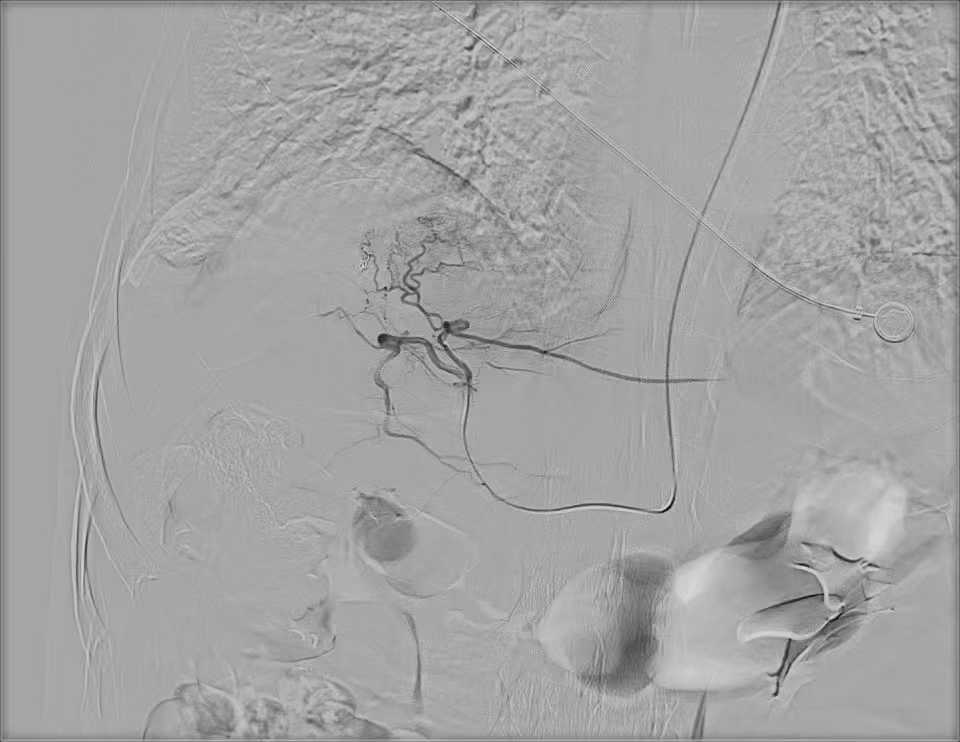

肝动脉化疗栓塞术示意图

手术经肱动脉入路,在不置入血管鞘、无需导管支撑的情况下,直接将微导管精准超选至肿瘤血管。经过医务人员精准操作,成功为患者完成治疗。手术创口仅0.5毫米。术后,患者在医护人员陪同下步行返回到病房。该技术让穿刺点压迫时间大幅缩短,且无需长时间卧床,改善了患者的就医体验。

据医务人员介绍,肝动脉化疗栓塞术(简称TACE),是中晚期肝癌的基石治疗方法。它通过导管将高浓度化疗药物精准注入肿瘤血管,并阻断其血流,从而实现精准控制肿瘤的目的。

传统TACE手术需要在血管中置入鞘管建立通路,术后会留下约3毫米的创口,患者往往需要长时间压迫穿刺点并严格卧床制动(通常需8-12小时),这在一定程度上影响了术后舒适度,成为传统介入治疗的“痛点”。